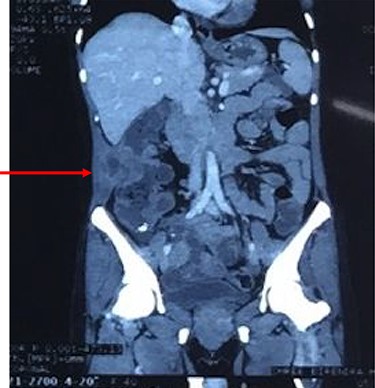

Coronal reconstruction of CT shows mass extending from colon and invading into anterior abdominal wall. Arrows indicate the point of exit of mass through the abdominal wall musculature.